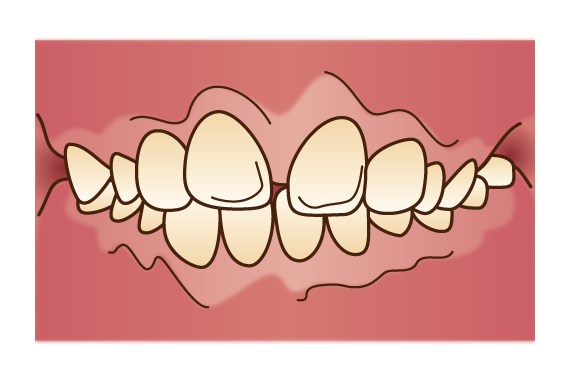

出っ歯

下の前歯よりも上の前歯が大きく突出した状態です。前歯が前方へ傾いているケースと骨格そのものが前に出ているケースがあります。前歯の表面や口腔内が乾燥しやすく、唾液の自浄作用を得られないことでむし歯のリスクが高まります。

下の前歯よりも上の前歯が大きく突出した状態です。前歯が前方へ傾いているケースと骨格そのものが前に出ているケースがあります。前歯の表面や口腔内が乾燥しやすく、唾液の自浄作用を得られないことでむし歯のリスクが高まります。